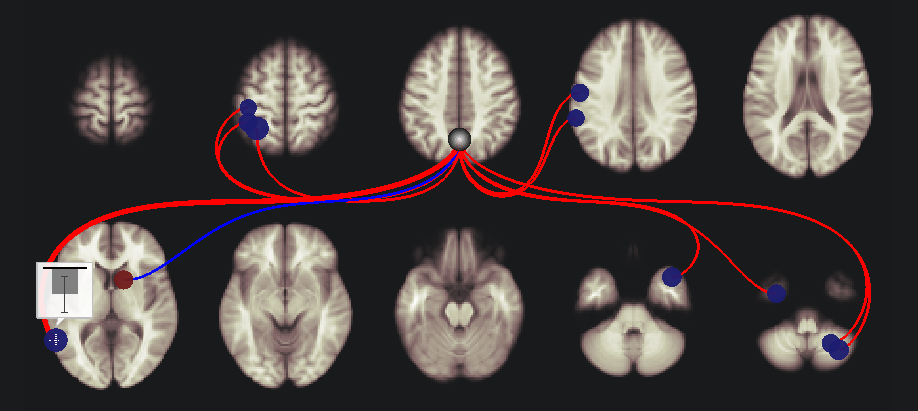

connを用いてfMRIによる脳機能結合の解析を行い始めたところです。初歩的な質問で恐縮なのですが、connでROI to ROIの機能結合を行って、結果を図に示したときに、TargetのROIが青と赤で示され、これが、正と負の相関であることはわかるのですが、SeedとROIのconnectionの線の色が、赤と青に区別されている意味がわかりません。ご教授していただけると幸いです。お忙しいところ誠に申し訳ありませんが、どうかよろしくお願いいたします。

赤い点と青い点があり、そして、赤い線と青い線があるわけです。

点:これは検定結果のEffect sizeを示しています。(connectivityではなく、検定結果を反映しています)

線:connectivityの絶対値が一番大きいものを示しています。

これを理解するうえで、一番左下の脳の2つの点(青と赤の点)に着目してみます。

まず、青い点をクリックしてみてください。

そうすると、点の上に棒グラフが表示されます。

そうしたら、画面の下の方にある “plot effects” をクリックしてみてください。

そうすると、以下のような図が出力されます。ここでは、年齢との相関をみていますので、この領域において、Effect sizeが-0.06弱ということがわかります。

続いて、plot effects の右側にある “plot values” をクリックしてみてください。

この例では、全体的には負なのですが、ひとつだけ +0.77のものがあり、それが一番大きいので、線は赤色になっています。

次に、その右側にある赤色の点をクリックしてみます。

そして、先ほどと同様にplot effectsを押します。

今回はeffect sizeが0.02よりちょっと大きいぐらいということがわかります。

(とりあえず説明のためにp値をものすごくゆるめているので値はあまり気にしないでください)

そして、plot valuesをクリックします。

そうすると、絶対値が大きいものは、-0.42となります。なので、青線です。

ということで繰り返しになりますが、

点:検定結果のEffect sizeで、正ならば赤、負ならば青となります。

線:各被験者のconnectivityの値で絶対値が一番大きいものを反映し、正ならば赤、負ならば青となります。

これでいかがでしょうか?